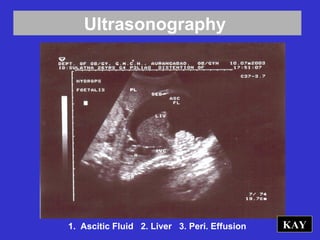

KAY1. Ascitic Fluid 2. Liver 3. Peri. Effusion

Ultrasonography KAY1. Ascitic Fluid2. Liver 3. Peri. Effusion